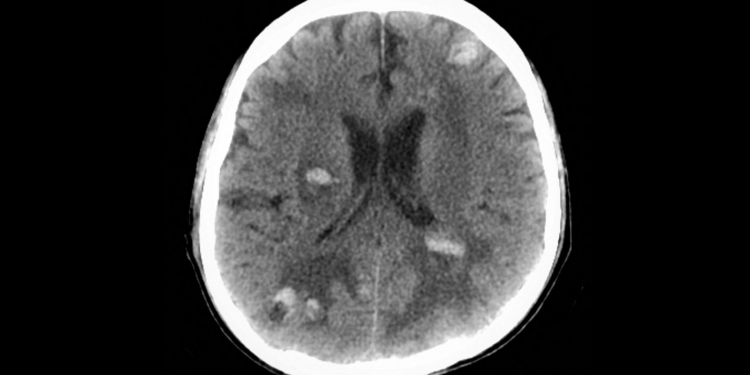

(MedPage Today) — GLP-1 receptor agonist use was associated with a lower risk of death in cancer patients with brain metastases and type 2 diabetes, a retrospective cohort study found.

Within 3 years of a first recorded brain metastasis, patients…